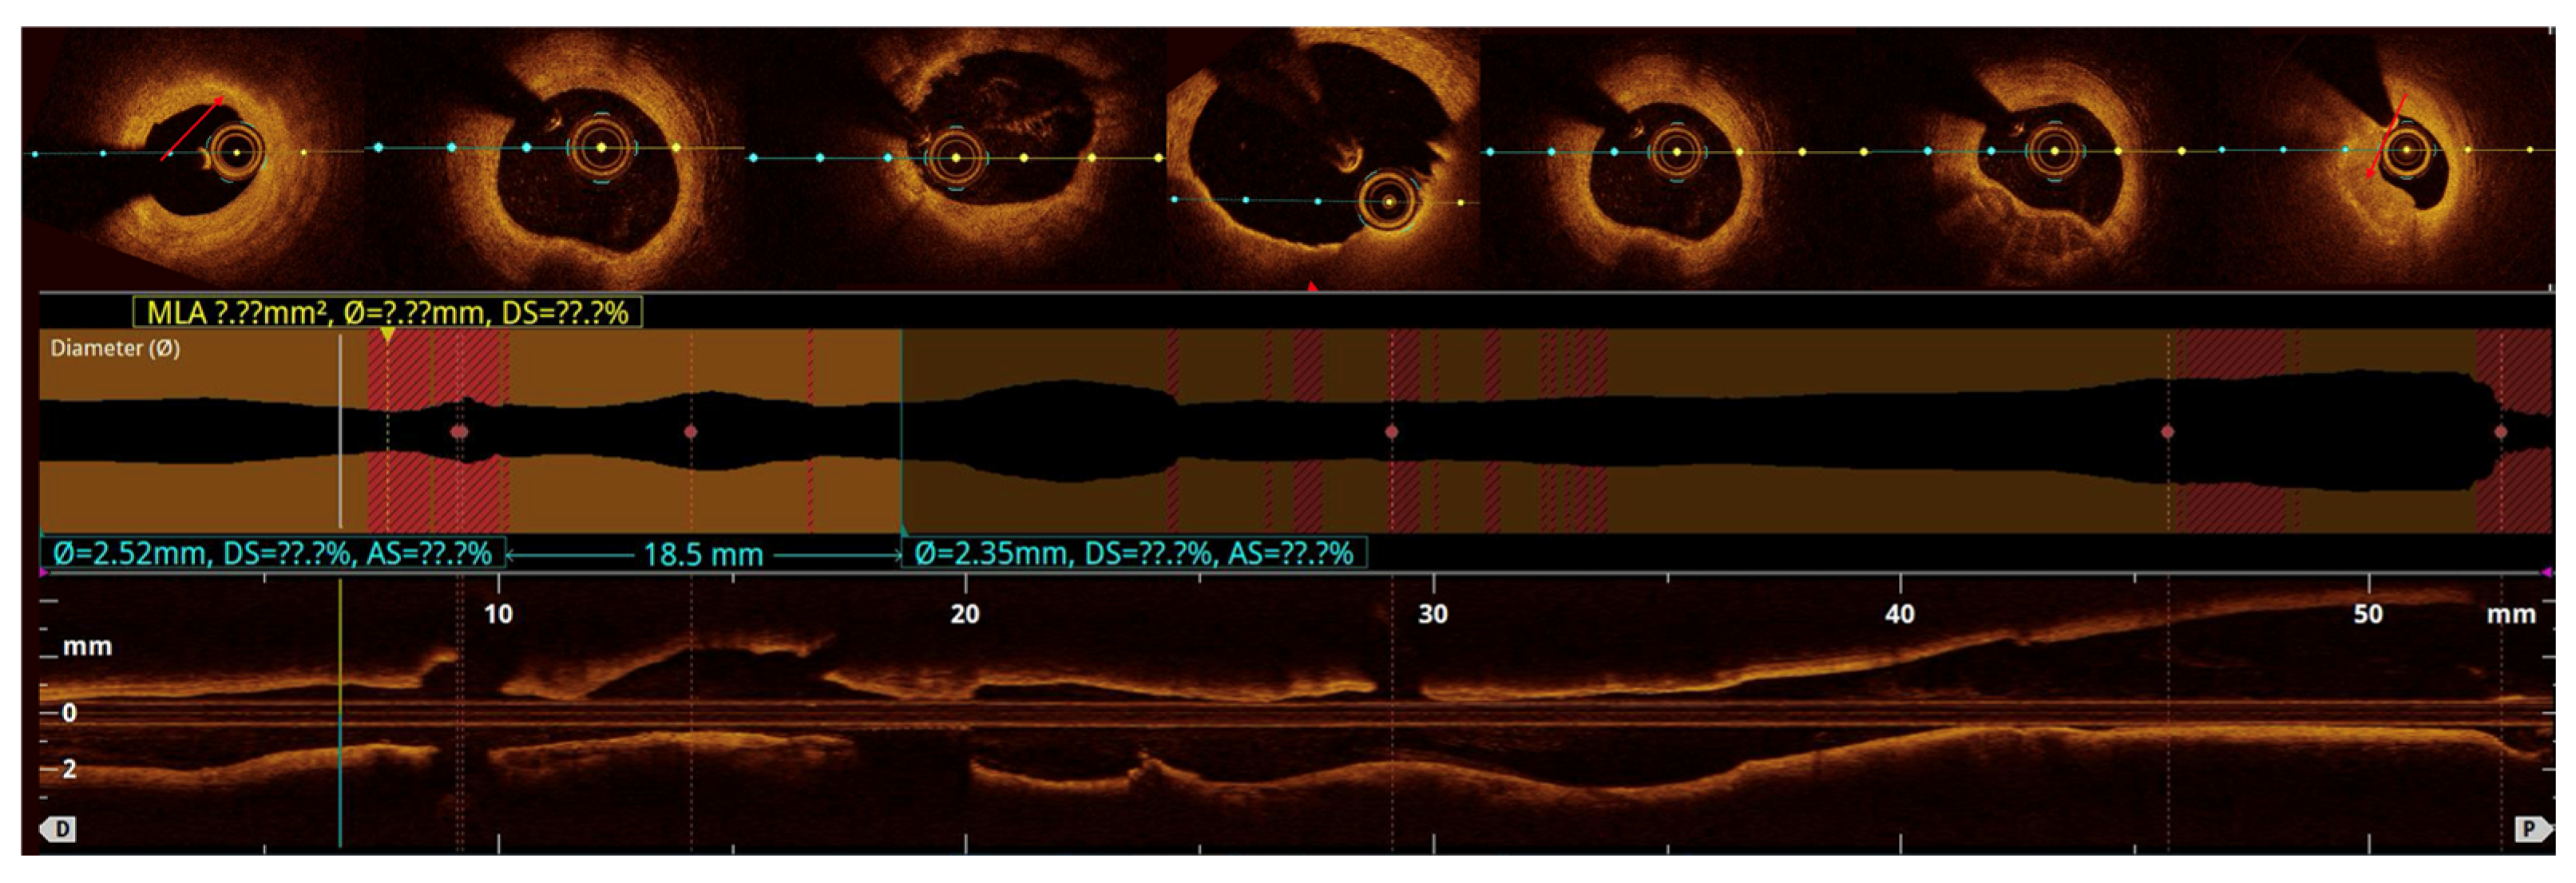

OCT-based analysis of aneurysmal remodeling:

Quantitative analysis was performed using optical coherence tomography (OCT) pullbacks (The OPTIS Next Imaging System by Abbott) obtained during optimal contrast clearing and a stable catheter position (

Figure 2). The aneurysmal segment was defined as the cross-section exhibiting the maximal luminal area within the visibly dilated portion of the vessel. The diameter was determined as the mean lumen and external elastic membrane (EEM) areas of proximal and distal reference cross-sections, located at least 5 mm away from the aneurysmal borders and appearing free or minimally affected by atherosclerosis, in accordance with established intravascular imaging standards [

10,

11]. When one or both adjacent segments were unsuitable due to diffuse disease, the least-diseased portion of the same vessel or the largest angiographically normal coronary artery was used as the reference [

2,

12]. CAA was defined as a focal luminal enlargement ≥1.5 times the reference diameter or >50% greater lumen area, consistent with prior angiographic and intravascular definitions [

13].

The maximal aneurysm diameter (right, within the aneurysmal segment) is measured perpendicularly across the lumen at the point of most significant dilation. The reference diameter (left) is measured perpendicularly across the lumen of the adjacent, non-dilated (normal) segment of the same vessel, proximal to the aneurysm. The aneurysmal ratio is calculated as the maximal aneurysm diameter divided by the reference diameter; values ≥1.5 indicate aneurysmal remodeling according to standard interventional definitions. The normal coronary vessel, with all its layers, is presented in

Figure 3.